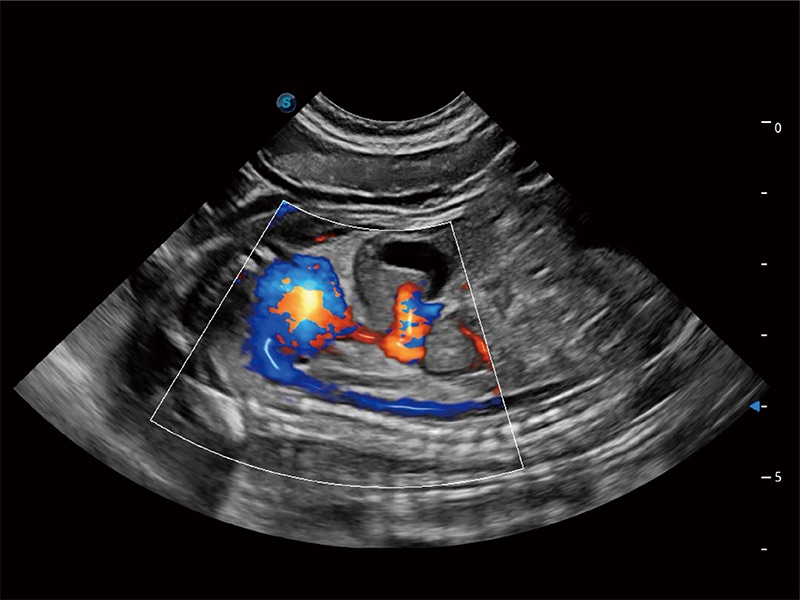

極大提升超低速微細(xì)血流的檢出能力,同時更精準(zhǔn)地濾除軟組織和超聲信號,為獸用醫(yī)生提供以往無法通過常規(guī)血流獲得的疾病診斷信息。

在傳統(tǒng)二維血流成像的基礎(chǔ)上,呈現(xiàn)血流的立體感,具有動感的生命力之美。即便是微小的血管也能輕松應(yīng)對,提高了血流的視覺敏感性。